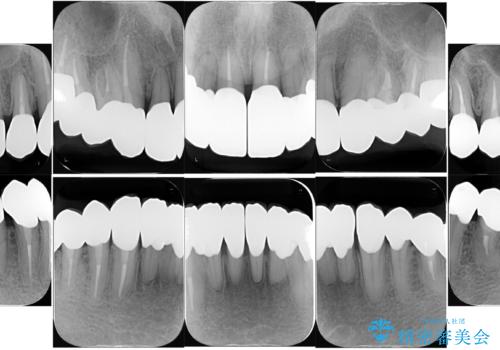

- 強い酸によって歯が広範囲にわたって侵食され、「歯がボロボロになった」と主訴に来院されました。詳細な診査の結果、重度の酸蝕症と診断。失われた歯質や咬み合わせの崩壊が著しいことから、単一の治療では対応が困難と判断し、矯正治療、インプラント治療、セラミック治療を組み合わせた総合的な治療計画を立案しました。矯正治療後に最終的にセラミックを用いて機能性と審美性を回復。患者様と綿密な話し合いを重ね、長期的な口腔内の健康維持を見据えた最適な治療を行いました。

酸蝕症の原因に関しては、医科のほうで解決済みでしたので、失われた機能、審美性の回復のため矯正治療によって歯並びと咬み合わせのバランスを整えセラミックによる修復を行ました。

保存できないと判断した歯は抜歯しインプラントにて治療をおこなっています。

矯正後、歯肉の形態不良のため、歯周外科を行い連続性を獲得しています。